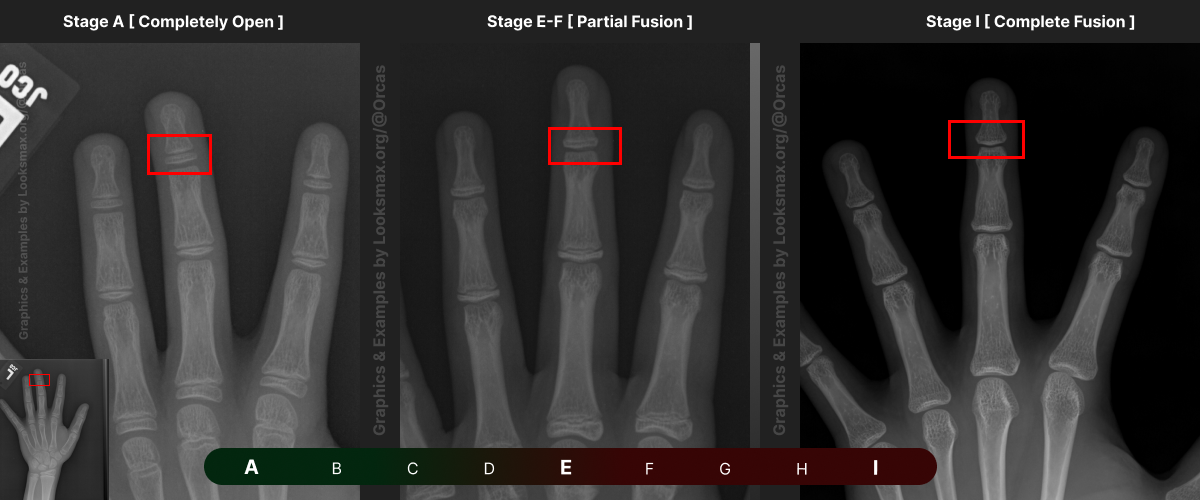

I added references for stages A (Completely unfused), E-F (Partial fusion, basically late stages of puberty), and I (Complete Fusion)

You will have to eyeball this now using your own xrays, I’ve given three examples and some wiggle-room for letters using a reference bar (green-red) below the image, write down your estimated guesses in a text file until you finish all 13 bones.

Don’t doubt yourself, eyeballing isn’t perfect but it still works well, just choose & continue.

Ex.

“My Radius looks more fused than the image from E-F, but its not as fused as I, it’s closer to the 2nd picture though, so I’ll rate it G” And continue

Bonetype: 3rd Proximal Phalanx

Check & use the chart below to figure out where you are. Then write your result on a piece of paper or a text file.